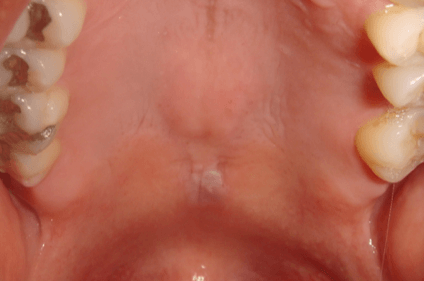

- Red patches (erythroplakia) or white patches (leukoplakia) in the mouth.

- A lump or thickening on the skin lining the inside of the mouth.

- Skin Lesions